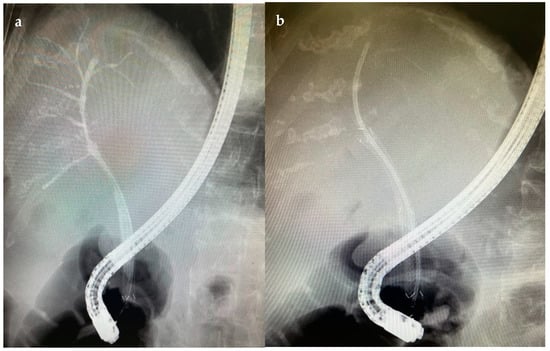

6.4.2. Endoscopic Retrograde Cholangiopancreatography (ERCP)

7.1.2. Endoscopic Nasobiliary Drainage (ENDB)